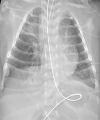

Results: A total of 39 studies with 850 pediatric patients were reviewed. 225 (26.5%) of patients had normal CT findings. Ground-glass opacities and consolidations were the most common CT abnormalities (384/625, 61.5%). Other findings were halo sign, interstitial opacities, bronchial wall thickening, and crazy-paving sign. Approximately 55% of patients had unilateral pulmonary findings. Most studies found peripheral and lower-lobe distribution to be a prominent imaging finding.

Conclusion: Our study showed that imaging findings in children were often milder and more focal than adults, typically as ground-glass opacities and consolidations with unilateral lower-lobe predominance, which have been regressed during the recovery time. A balance must be struck between the risk of radiation and the need for chest CT. If still necessary, low-dose CT is more appropriate in this age group. Albeit, due to the limited number of reported pediatrics with COVID-19, and the lack of consistency in CT descriptors, further work is still needed in this regard.